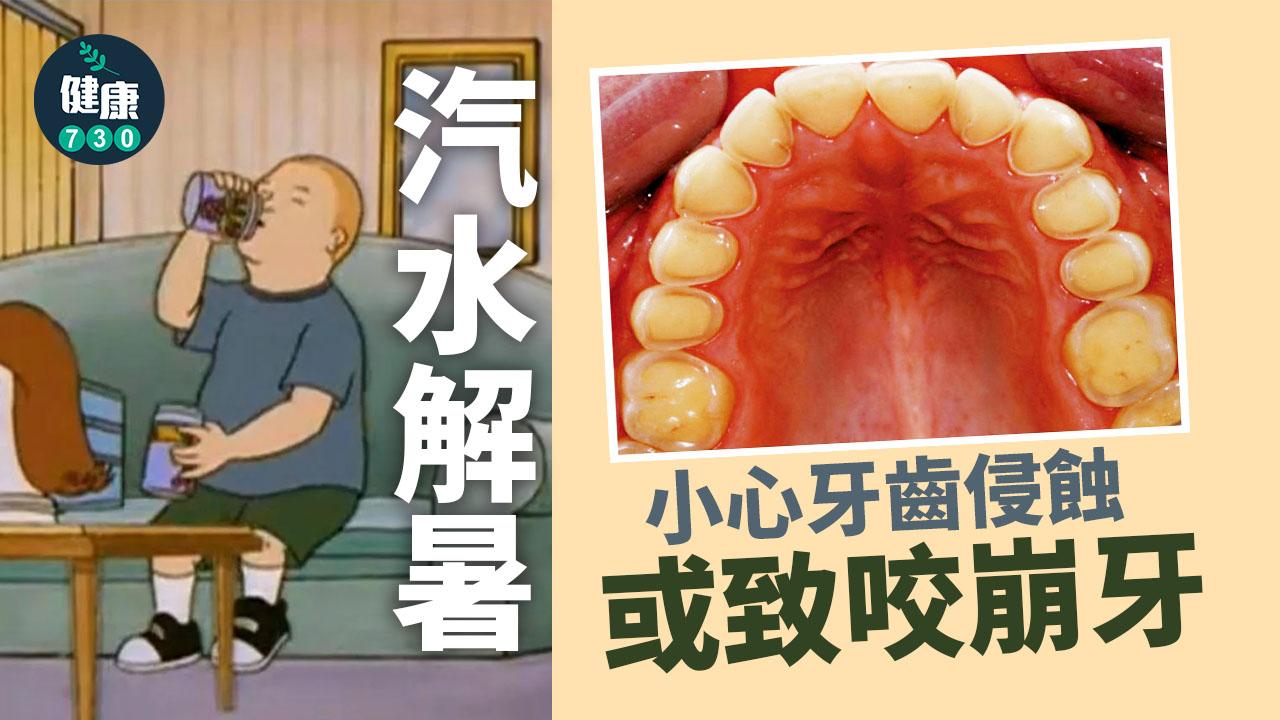

甜飲解暑 小心牙齒侵蝕

天時暑熱,要常補充水分,但不少人更愛喝汽水、台式飲品等。經常飲用含酸性或糖分飲品會使牙齒侵蝕的風險大大提高,我們日常應該要留意口腔衛生,減少口腔與酸性物質接觸,避免牙齒表面的琺瑯質流失。

琺瑯質的破損主要有兩類成因,首先是物理性的磨蝕,例如磨牙、刷牙太用力、喝凍飲會咬冰等咬硬物的習慣等;另一種就是酸性侵蝕。黃凌旻續指,「如處於pH5.5或以下酸性環境,琺瑯質便會開始流失。當進食後,口腔殘餘的糖分會被細菌分解成酸性物質;另外,常飲汽水(含有檸檬酸)、過量進食水果如蘋果或西柚(pH3至4)都易令琺瑯質被侵蝕。」

當琺瑯質變薄,便會透出偏黃色的象牙質。

或致咬崩牙

初期牙齒侵蝕未必有明顯徵狀,但如情況惡化,或出現牙齒凹痕、變黃、敏感、蛀牙等,由於象牙質比琺瑯質較易被侵蝕,或使剩下的琺瑯質失去支撐,變得脆弱容易咬崩,嚴重影響日常生活。黃凌旻於臨床上遇過更嚴重情況,「除了牙齒表面的損耗外,牙房亦已收縮,並形成牙房結石,本屬人體自我保護機制,但結石或影響牙房的供血情況,可使牙神經慢慢枯死、牙齒容易受到感染。」